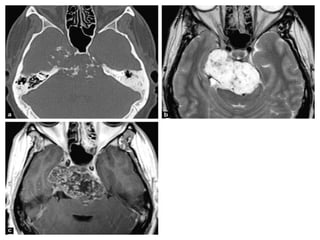

• #41 Chondrosarcoma: large mass localized on the right petroclival fissure invading the right cavernous sinus and extending to the posterior fossa with mass effect on the pons. CT shows stippled calcifications and petrous apex erosion (a). This mass is strongly hyperintense on T2-wi (b), and shows heterogeneous enhancement after contrast (c).